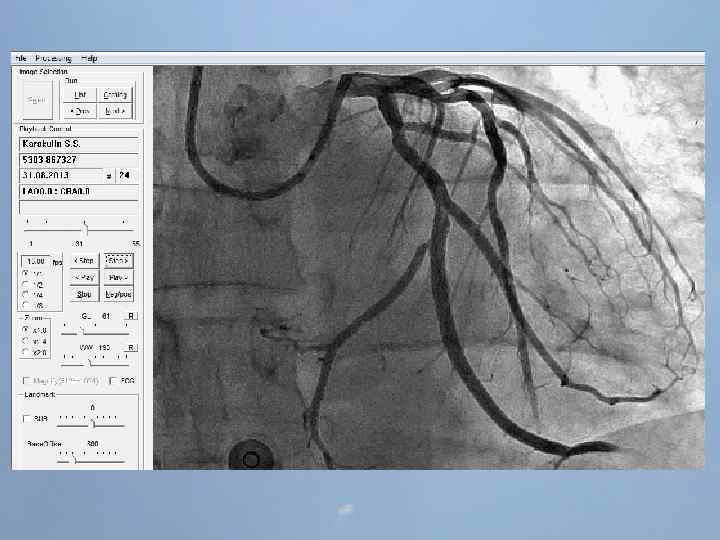

Пациент Б. , 54 года 29. 08. 13 около 10: 00, находясь на рабочем месте, почувствовал боль в груди. После 2 -ух приемов нитроспрея боль не уменьшилась, вызвал СМП. В 10: 20 первой бригадой СМП зафиксирован подъем ST на ЭКГ, начата ТЛТ, вызвана реанимационная бригада. В 10: 50 на месте вызова в присутствии реаниматолога у пациента развивается остановка кровообращения по типу фибрилляции желудочков. Выполнялась СЛР с непрямым массажем сердца, ИВЛ мехом, дефибрилляцией. В течение транспортировки фибрилляция рецидивировала еще 4 раза. Пациент доставлен в ООКБ в 11: 30, минуя приемное отделение госпитализирован в ОРИТ ОИМ.